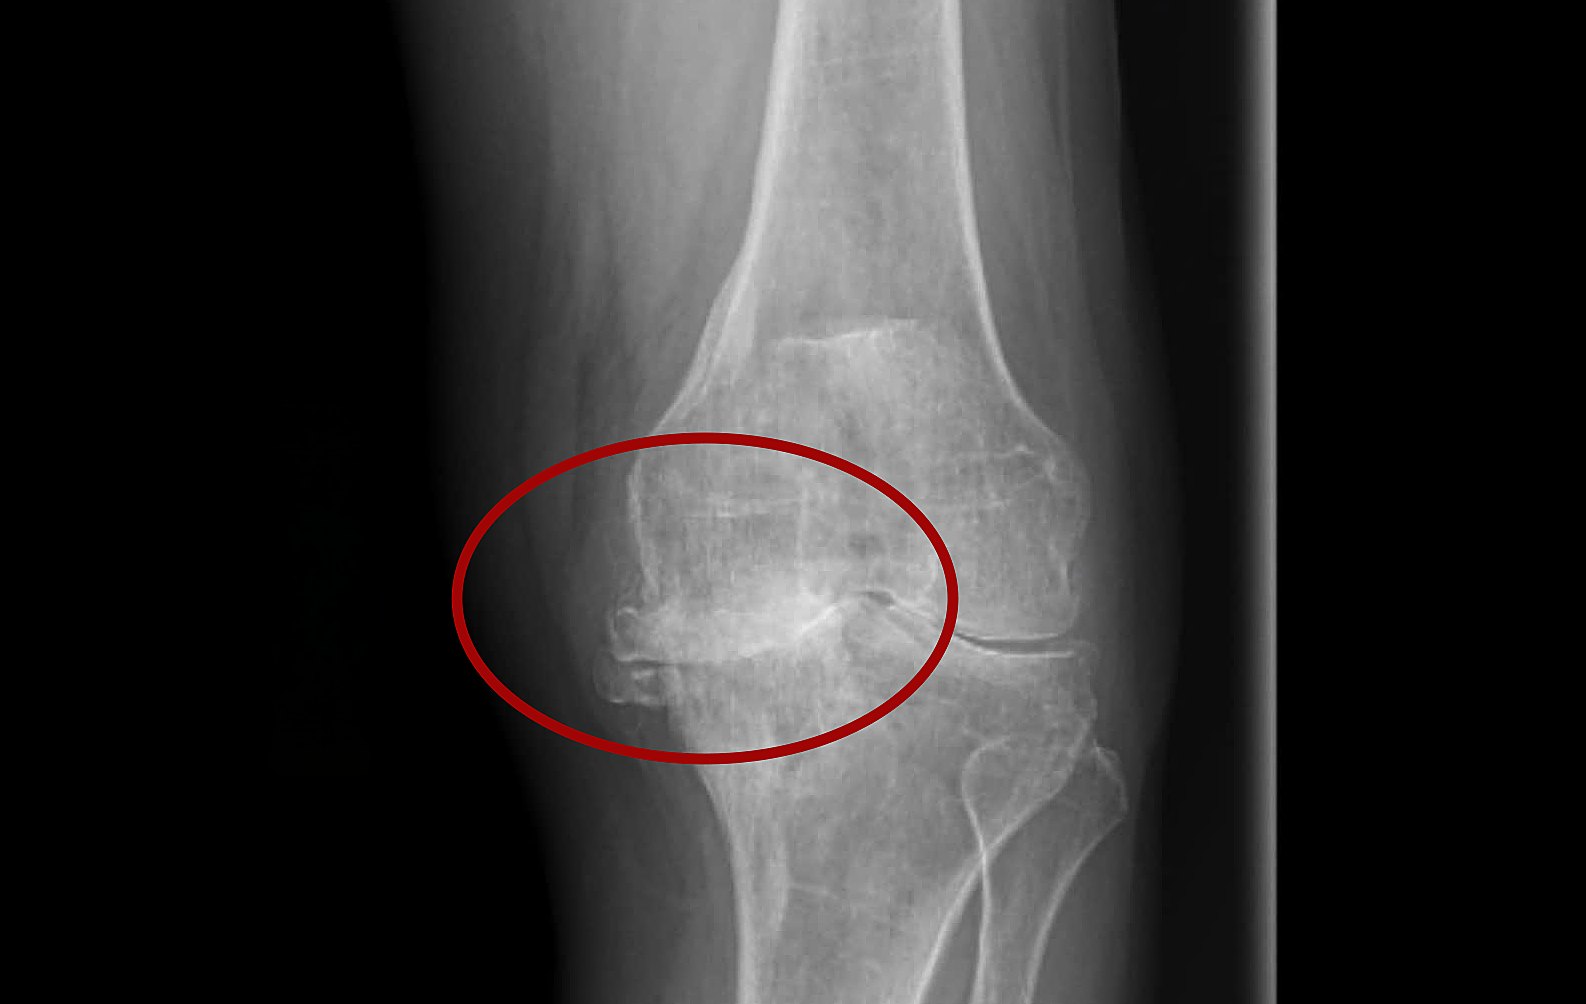

Severe axial deviation caused a medial tibial plateau fracture. *Photo: Tam Anh General Hospital*

Ms. Thanh developed knee osteoarthritis following an accident. Medication proved ineffective, and her pain progressively worsened. X-ray results at Tam Anh General Hospital TP HCM revealed that Ms. Thanh's right leg suffered from ligament laxity, end-stage knee osteoarthritis, and complete cartilage degeneration. This condition caused the two ends of her knee bones to rub together during movement. The prolonged issue led to joint deformity, severe bowing of her right leg, and her knee hyperextending by approximately 45 degrees.